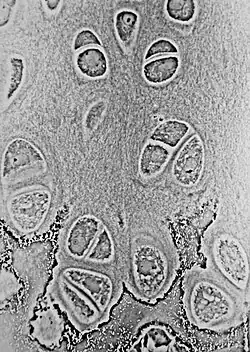

Der hyaline Knorpel ist die meistverbreitete Knorpelart. Am Rand des hyalinen Gewebes haben die Chondrozyten eine elliptische Form, wobei die Längsachse parallel zur Knorpeloberfläche verläuft – die Knorpelhöhle ist durch Kollagenfasern (Typ II) von der Umgebung abgegrenzt. Im Inneren des Knorpels sind sie rundlich mit fingerförmigen Fortsätzen und kommen in Gruppen von bis 8/10 Zellen vor, die durch Teilung aus einer einzigen entstanden sind (isogene Gruppen). Mehrere Knorpelhöhlen werden ebenfalls durch Kollagenfasern zu funktionellen Einheiten, den Chondronen, zusammengefasst. Diese sind druckelastisch.